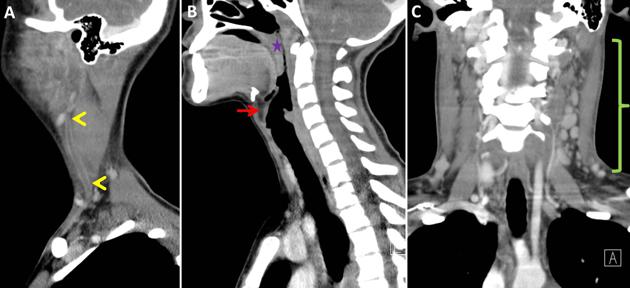

What's the Diagnosis?